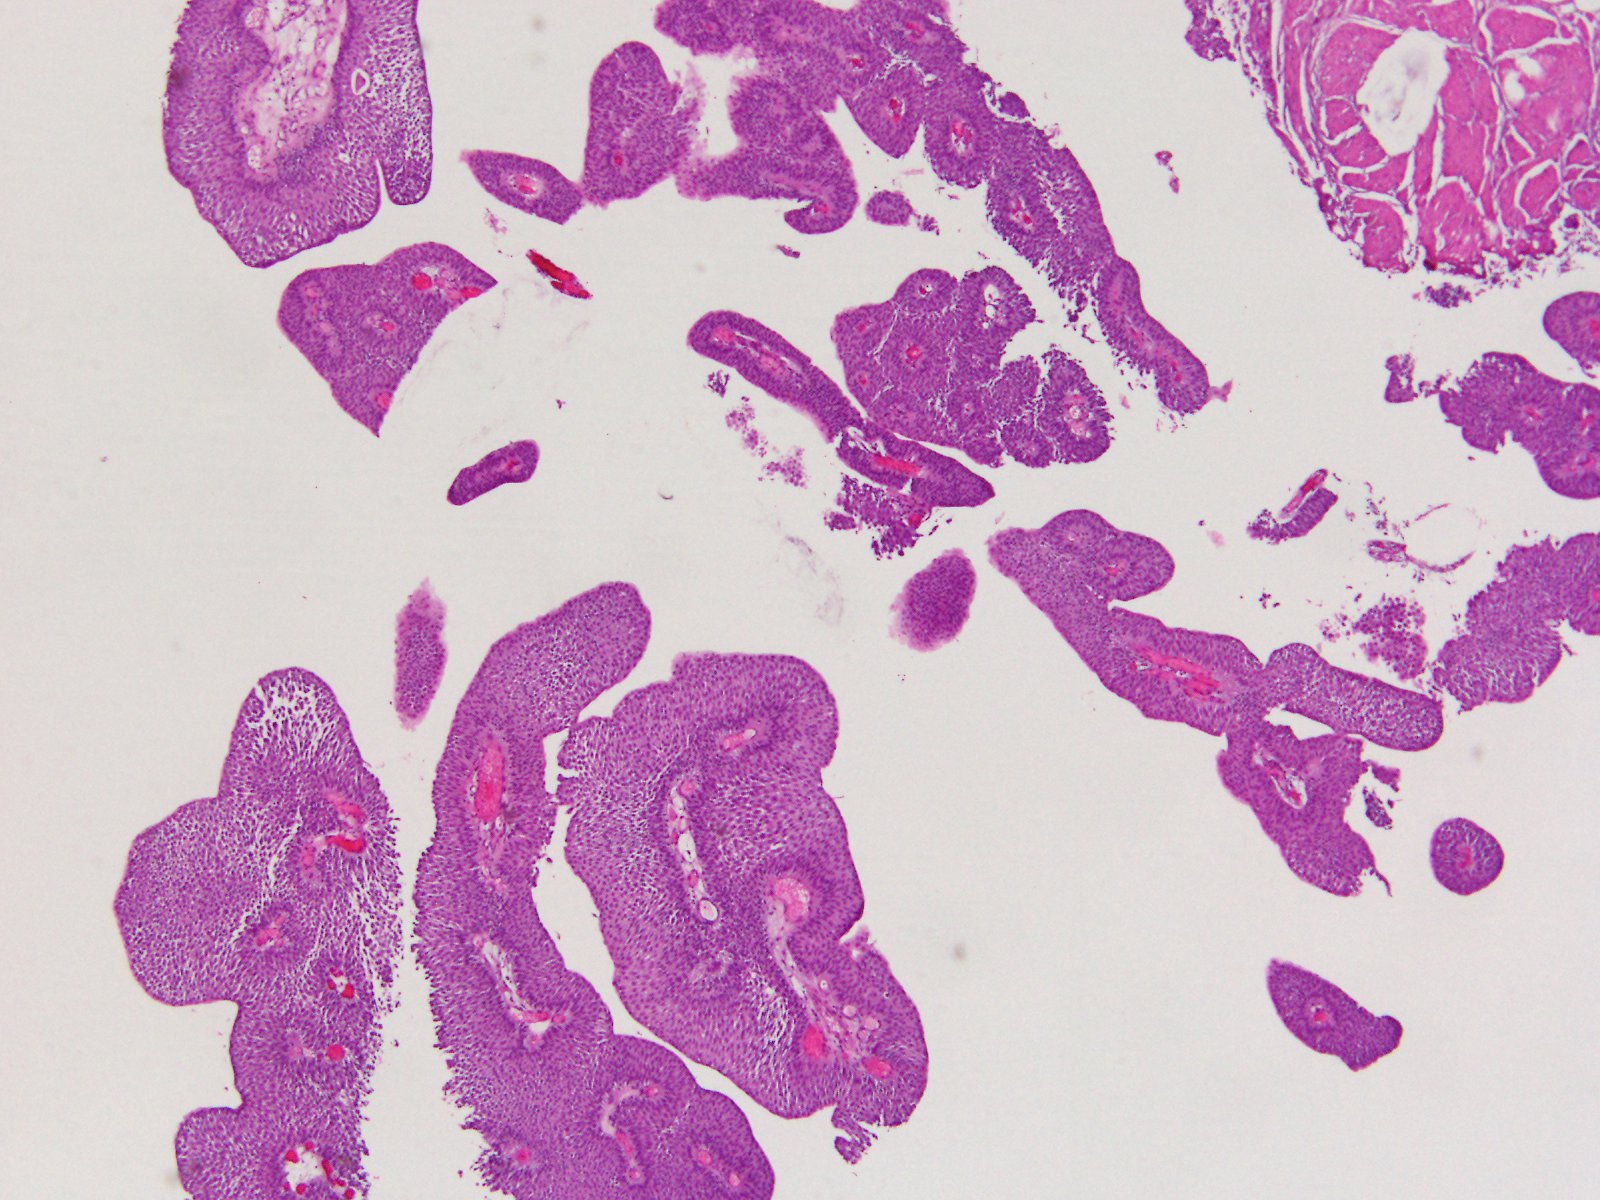

Consensus grade: PUNLMP

87 y/o. Bladder tumor.